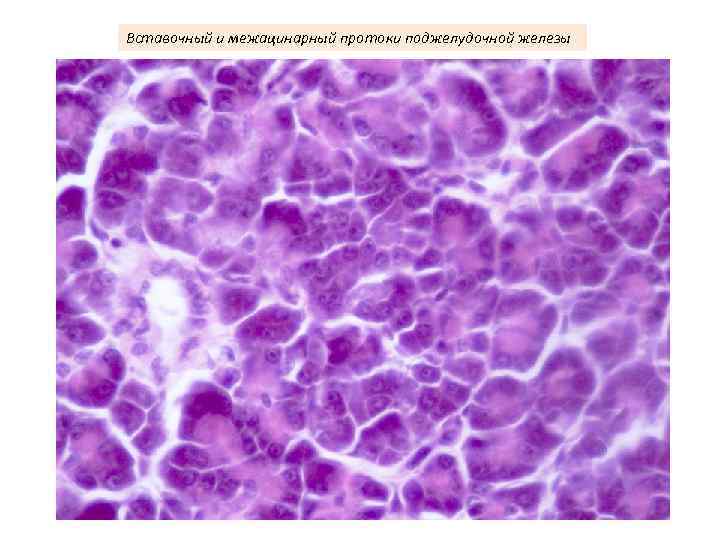

Вставочный и межацинарный протоки поджелудочной железы